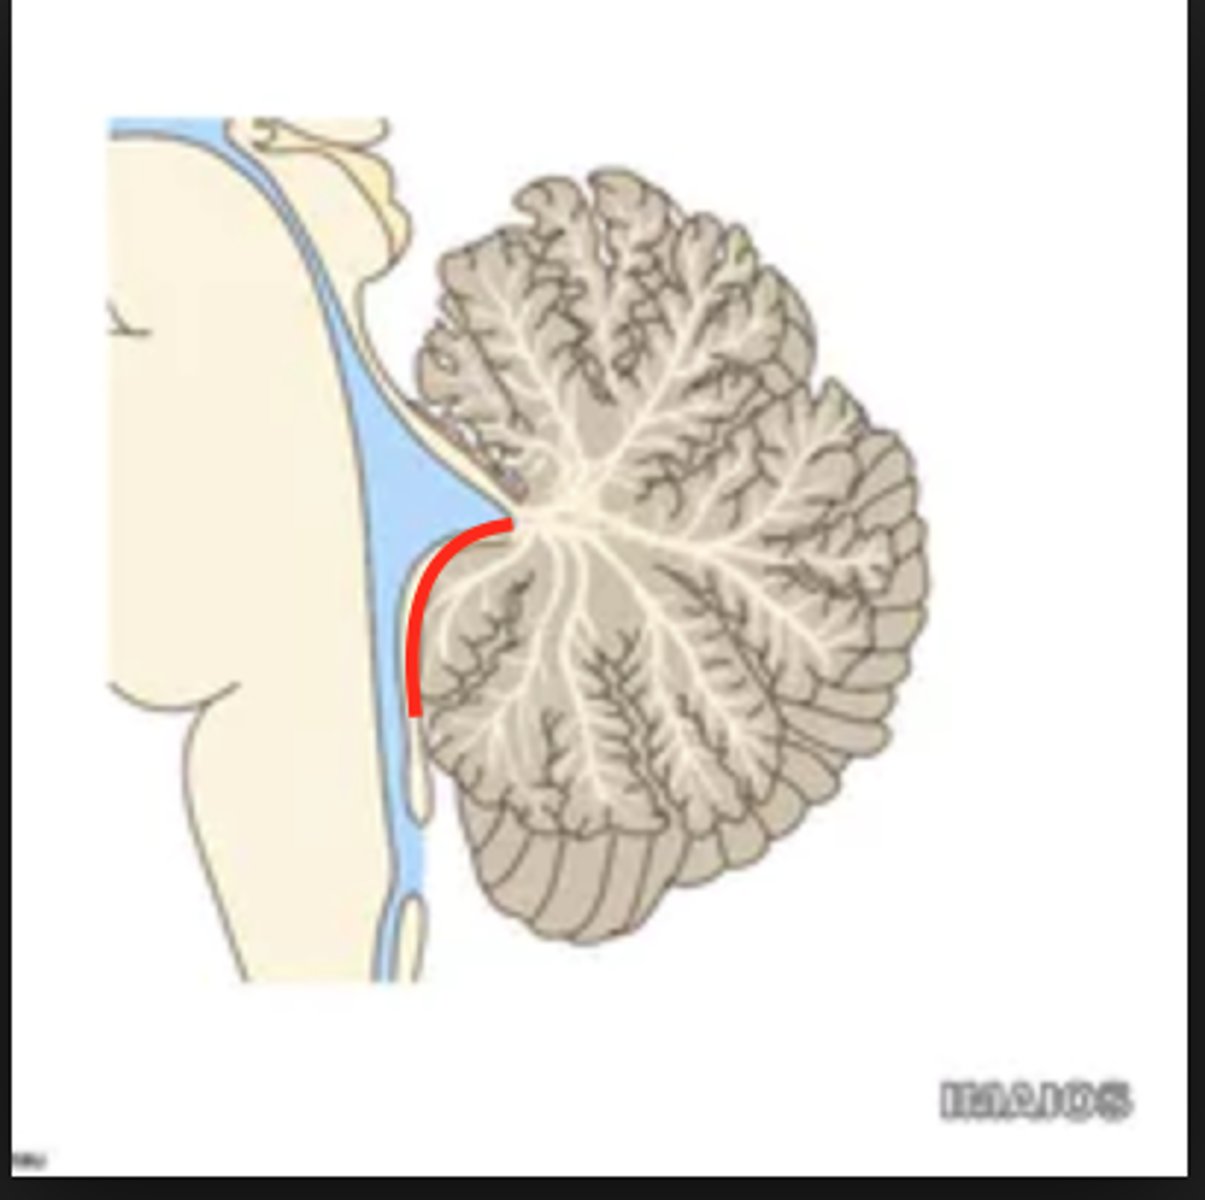

inverted V shaped interval between the superior cerebellar peduncles that is filled by a thin layer of white matter

superior medullary velum

lower portion of the roof of the 4th ventricle formed by a thin layer of pia mater and ependymal cells

inferior medullary velum

structure attached to the ventral surface of the inferior medullary velum in the 4th ventricle that helps form CSF

choroid plexus

opening in the caudal aspect of the inferior medullary velum that allows CSF from the 4th ventricle to flow into the cisterna magna of the subarachnoid space

foramen of Magendie (or median aperture)

What mostly forms the lateral walls of the 4th ventricle?

inferior cerebellar peduncles and choroid plexus

openings in the 4th ventricle that allows CSF to flow from the 4th ventricle into the pontine cistern of the subarachnoid space

foramen of von Luschka (or lateral apertures)